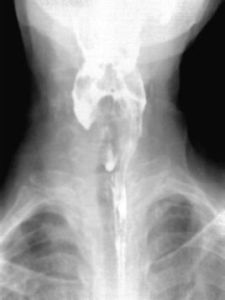

充盈缺損:是放射科的術語,在X射線下用鋇餐檢查胃或腸時,鋇劑塗布的輪廓有局限性向內凹陷的表現,為腔壁局限性腫塊向腔內突出,造成局部鋇劑不能充盈所致。(人衛影像學第七版)。是放射科的術語,指在鋇劑造影時,由於病變向腔內突出形成腫塊,即在管腔內形成占位性病變,所以造成局部造影劑缺損。惡性腫瘤造成的充盈缺損常不規則,而息肉造成的充盈缺損境界光滑規整。

疾病病因 臨床表現 醫技檢查 診斷依據 容易誤診的疾病觀察胃體和竇部充盈相,注意有無龕影,充盈缺損、狹窄,胃竇部的張力、蠕動...是否正常,胃壁是否柔軟,有無龕影、充盈缺損。胃的張力、位置。十二指腸球和...充盈更為適當,更有利於顯示病變。發現龕影和充盈缺損時,應使用壓迫法。在中...

病因 臨床表現 診斷檢查 併發症 治療檢查可見食管腔充盈不規則、狹窄、管壁僵硬、擴張度差等X 線徵象,酷似髓質型...